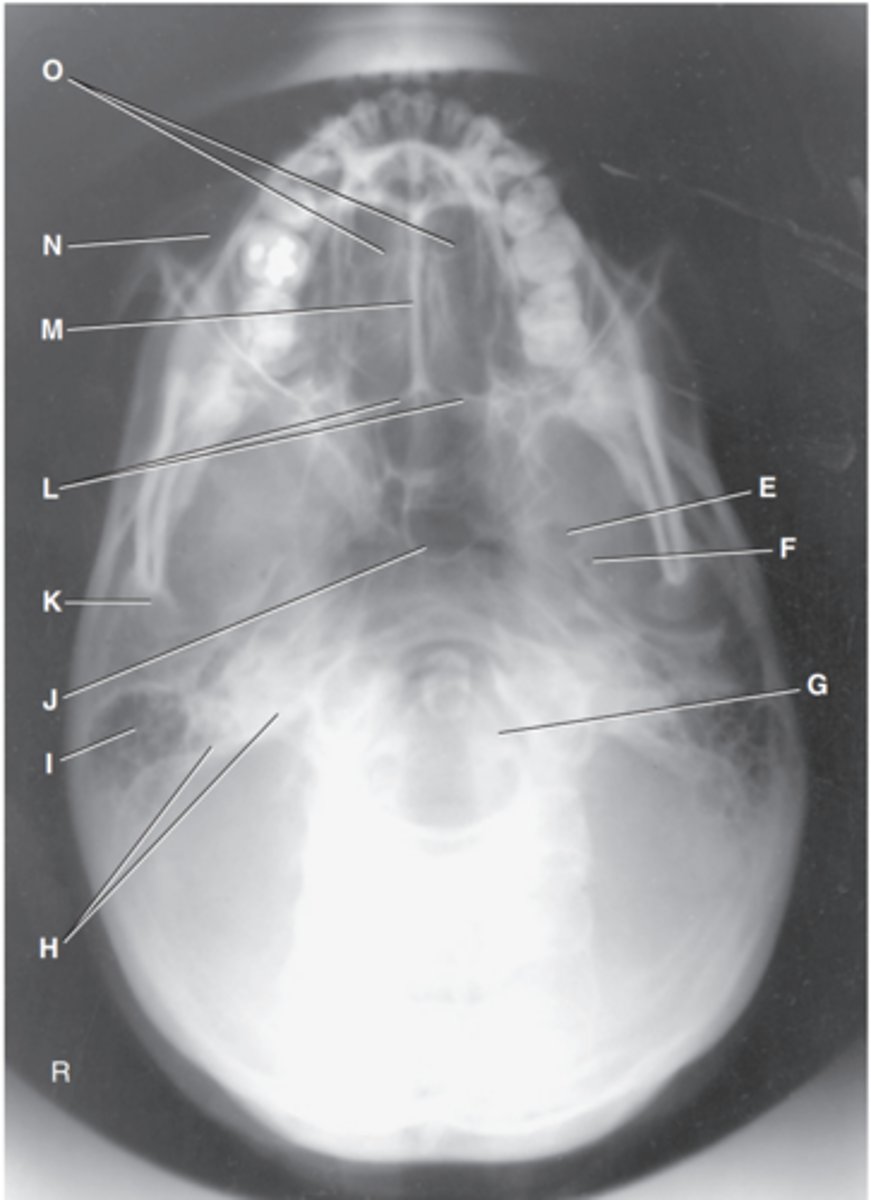

Foramen magnum

Label J

Zygomatic arch

Label A

Palatine process of maxilla

Label B

Horizontal process of palatine bone

Label C

Pterygoid hamulus of sphenoid

Label D

Foramen ovale of sphenoid

Label E

Foramen spinosum of sphenoid

Label F

Foramen magnum

Label G

Petrous pyramid of temporal bone

Label H

Mastoid portion of temporal bone

Label I

Sphenoid sinus in body of sphenoid

Label J

Condyle of mandible

Label K

Posterior border of palatine bone

Label L

Vomer

Label M